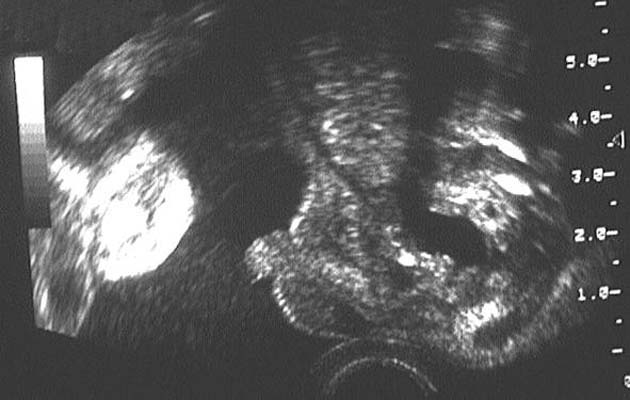

- Les surrénales :

Souvent difficiles à visualiser.

En coupe transversale, bandelettes parfois ovoïdes, hypo-échogènes, à grand axe dirigé en avant et en dedans avec un centre hyper-échogène.